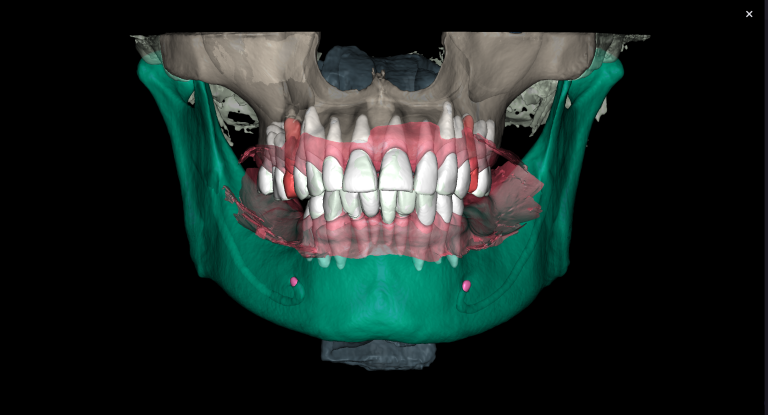

Task: Plan the implant treatment for the replacement of teeth 16 (Universal 3) and 17 (Universal 2), reduce the time required for surgical template fabrication, and improve the accuracy of its fit. Using the “STL” module of Diagnocat, it is possible to create a 3D reconstruction of cone-beam computed tomography (CBCT) and virtual models of templates. To achieve this, intraoral scan data is uploaded into the module, and a suitable CBCT is selected for merging.

Solution: Diagnocat AI provides an advanced solution for identifying CBCT structures using machine learning and artificial intelligence technologies. By combining STL and DICOM data in a unified coordinate system, Diagnocat minimizes errors when creating template models.